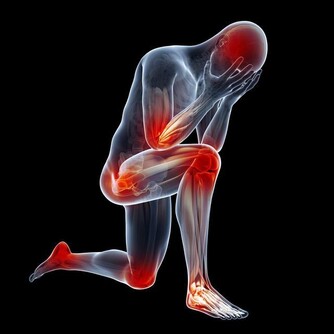

免疫力下降,有哪些症狀?

想要知道自己免疫力好不好,不妨簡單測試一下。如果以下表現佔了一半,該敲醒“警鐘”了~

免疫力低下,容易生病怎麼辦? 不妨做4件事,提升免疫力

1、經常感冒

• 免疫力下降的人,最直觀的表現就是容易感冒發燒,尤其在季節交替、溫度驟變之時,更為高發;

• 一年中感冒次數超過3次,且病程一般有7天甚至10天以上;

• 感冒還反反复复,即康復後,過幾天又發作了。

2、身體疲勞

經常感到全身疲憊,稍微做點事就會覺得累;每天即便睡眠充足,睡眠時間超過9個小時,但仍覺得困倦,精神不振,還容易分神。

3、腸胃不適

易患腸胃病。比如,一吃生冷或重口的食物,就會出現胃痛、腹瀉等症狀;或在外吃飯,同樣的食物別人吃了沒事,但自己卻肚子疼,甚至上吐下瀉。

4、癒合能力差

身體淤青後很難消下去;或者傷口相比其他人來說,癒合得很慢,很可能過了一段時間後還沒有完全癒合,而且還容易受到感染,出現紅腫、流膿的情況。

5、經常發生口腔潰瘍

6、頻發炎症

經常咳嗽,容易出現支氣管炎、咽喉炎、肺炎等炎症;如果是本身有哮喘的人,哮喘也會反復發作。